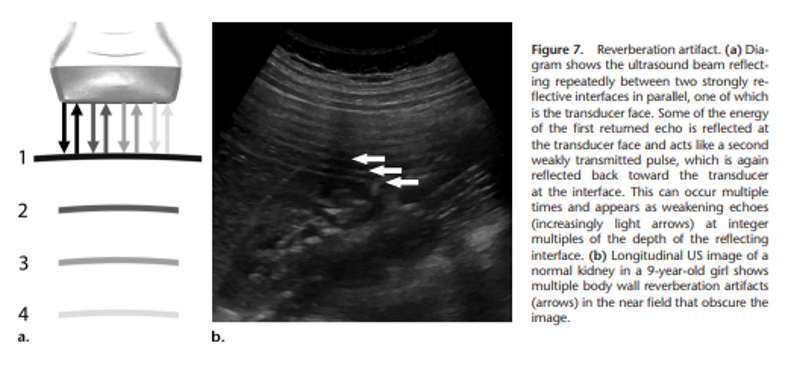

The artifact shown is reverberation caused by back and forth reflection of the ultrasound beam between 2 closely spaced interfaces. These reverberation echoes appear as multiple equally spaced lines, which decrease in intensity with increasing depth. This artifact is often caused by highly reflective interfaces, e.g., metallic objects or calcification in tissues.

reverberation artifact:

multiple equidistance echoes

comet tail artifact is a form of reverberation, but the two parallel highly reflective surfaces are closer together –> sequential echoes are closely spaced

spce between reflectors may be < SPL (minimal distance needed for axial res)

Reason you see a triangle and not a square: later echoes get attenuated and have decreased amplitutde. Decreased amplitude is manifested on the displayu as decreased width. So you get a tapering triangle

ring down artifact

sound wave encounters fluid trapped between a tetrahedron of air bubbles. The vibrations create a nearly continuous sound wave transmitted back towards the probe